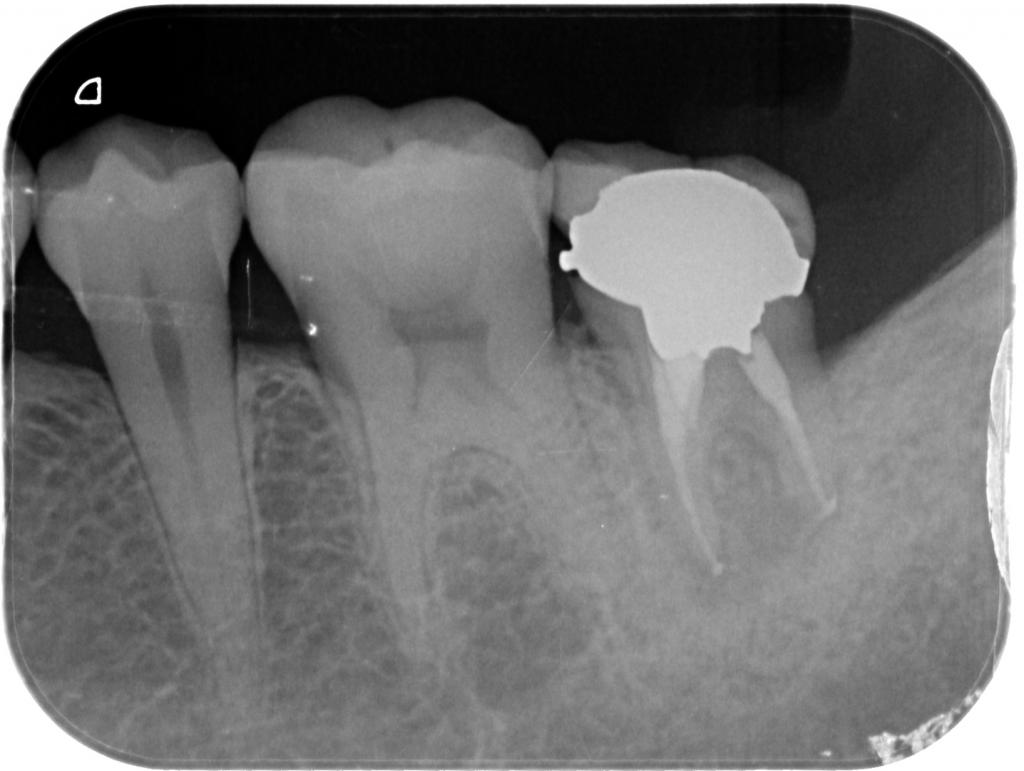

• 根管治療事例にNO.34を掲載しました。

根管治療事例にNO.34を掲載しました。